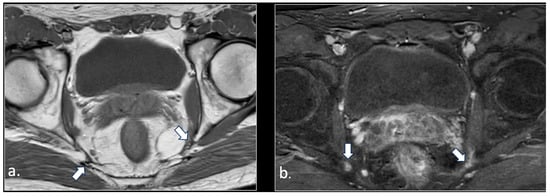

MRI in Chronic Pudendal Neuralgia: Diagnostic Criteria and Associated Pathologies

by Michele Gaeta, Sofia Turturici, Karol Galletta, Carmelo Geremia, Attilio Tuscano, Aurelio Gaeta, Marco Cavallaro, Salvatore Silipigni and Francesca Granata

Background/Objectives: Chronic pudendal neuralgia is a relatively rare condition in the general population, with an incidence of 1%. Although diagnosis of pudendal neuralgia is mainly clinical, Magnetic Resonance Imaging (MRI) is commonly performed to obtain further information. However, clear criteria and guidelines for MRI diagnosis and the clinical–radiological correlation are still not definite. Methods: We reviewed 81 patients with chronic pudendal neuralgia, studied by an MRI designed protocol for a pelvis and pelvic floor examination. A key element of the protocol was the use of a diffusion-weighted imaging (DWI) technique with echo planar imaging (EPI) sequence (b-values of 0, 100, and 600) for the neurographic evaluation of the nerve. Results: MRI examination revealed DWI abnormalities in 42/81 patients. Pudendal nerve abnormalities were unilateral in 33/42 patients and bilateral in 9/42. Moreover, in 23/42 patients, pathologies related to a high probability of neuropathy have been identified. Conclusions: This study highlights the role of pelvic MRI as a valuable imaging modality in the evaluation of patients with chronic pudendal neuralgia. In the study protocol we propose, an essential role is played by the DWI technique, which improves the visual definition of the pudendal nerve and related anatomical structures. By focusing on anatomical visualization and structured image interpretation, our work provides a practical imaging-oriented contribution to a field in which standardized MRI evaluation is still lacking. Full article